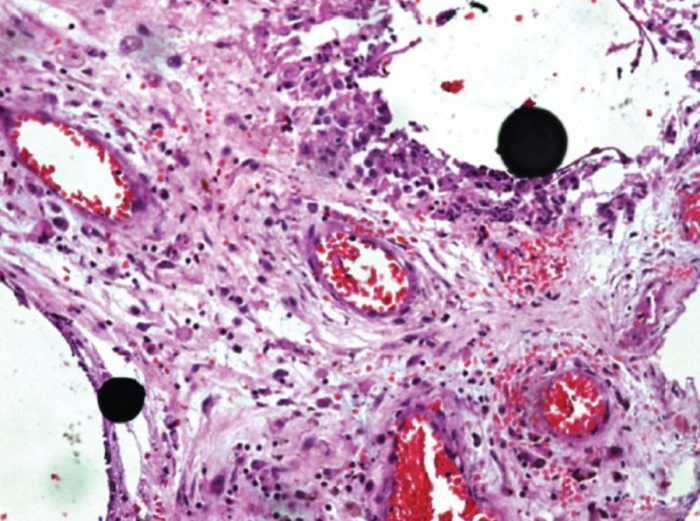

Окрашенный гематоксилином и эозином срез (× 10), показывающий капли ртути в кистозных пространствах, окруженных клетками хронического воспаления